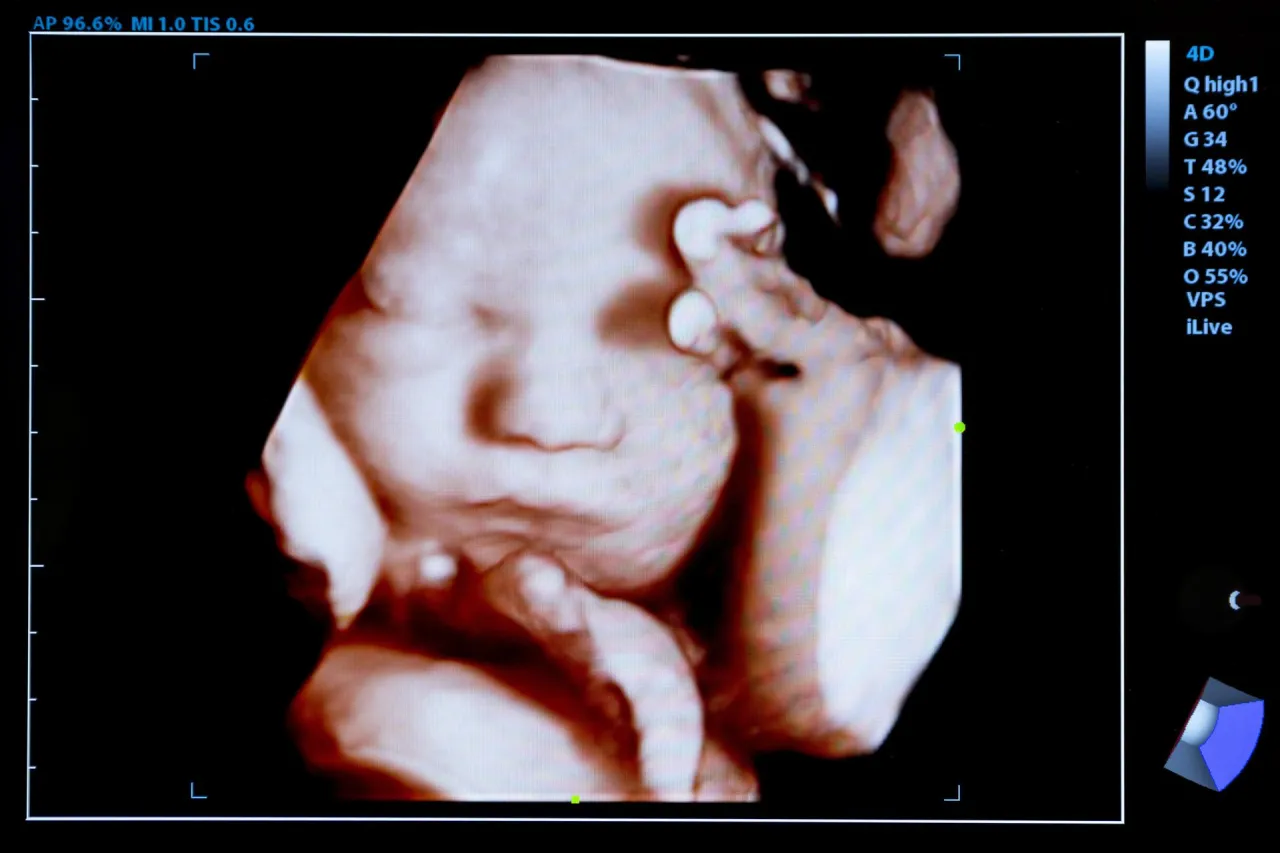

Dziecko w brzuchu matki ma zdolność odbierania emocji i sygnałów z otoczenia, co ma ogromne znaczenie dla jego rozwoju. Badania pokazują, że emocje matki mogą wpłynąć na płód już od wczesnych tygodni ciąży, m.in. poprzez zmiany hormonalne, które przenikają przez łożysko. Zrozumienie, jak te emocje wpływają na zawiązujące się życie, pozwala lepiej dbać o przyszłe matki oraz ich dzieci.

Dziecko zaczyna rozwijać zdolności emocjonalne już w pierwszym trymestrze ciąży, a kluczowym momentem jest około 16. tydzień. W tym czasie rozwija się aparat słuchowy, co pozwala mu reagować na dźwięki, takie jak głos matki. Odbieranie tych bodźców emocjonalnych jest fundamentalne dla długoterminowego rozwoju płodu i jego zdolności do interakcji z otoczeniem. W miarę jak ciąża postępuje, dziecko staje się coraz bardziej wrażliwe na emocje matki. To, jak matka przeżywa swoje emocje, może mieć znaczący wpływ na rozwój dziecka, kształtując jego reakcje na różnorodne bodźce oraz emocjonalne zdrowie w przyszłości.Wpływ emocji matki na płód – co mówią badania